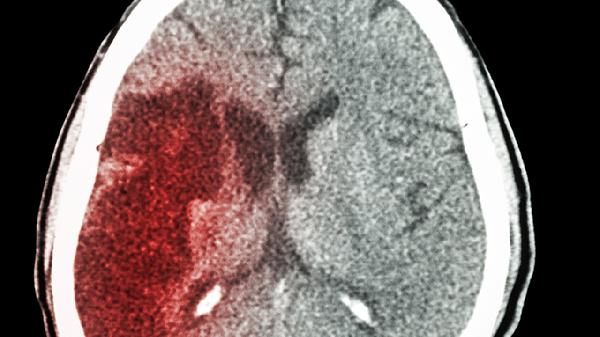

安宫牛黄丸在脑梗急性期有一定辅助作用,但不能替代正规治疗。脑梗的治疗需要综合药物、手术和康复手段,安宫牛黄丸可作为辅助用药,但需在医生指导下使用。

安宫牛黄丸是一种中药制剂,主要成分包括牛黄、麝香、珍珠等,具有清热解毒、醒神开窍的功效。在脑梗急性期,安宫牛黄丸可能通过改善脑部血液循环、减轻脑水肿、保护神经细胞等方式发挥一定作用。研究表明,安宫牛黄丸对缺血性脑损伤有一定的保护作用,但其疗效仍需更多临床数据支持。